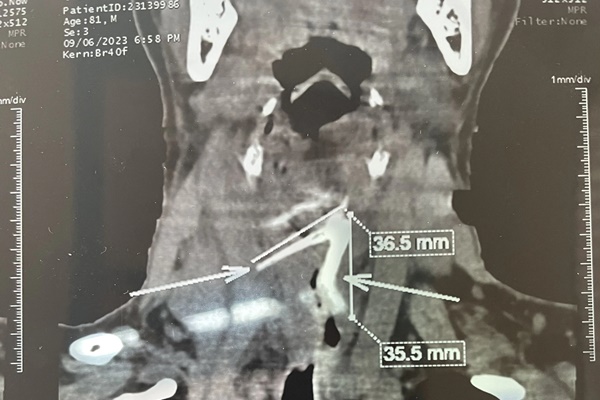

Khai thác tiền sử ghi nhận anh T. bắt đầu có các triệu chứng này sau khi ăn cá nhưng không có biểu hiện hóc xương. Bác sĩ chỉ định siêu âm bụng và chụp CT có cản quang, phát hiện dị vật nên chuyển vào Khoa Ngoại Tiêu hoá điều trị.

Bác sĩ chuyên khoa 2 Chung Hoàng Phương, Khoa Ngoại Tiêu hóa, Bệnh viện Nhân dân Gia Định cho biết ngay khi vào ổ bụng vùng bờ dưới gan trái của bệnh nhân, phẫu thuật viên phát hiện đầu xương cá nhô ra và tiến hành rút xương. Sau đó, mở tiếp vào vùng sau dạ dày, bờ trên tụy có khối áp xe to phập phồng kích thước 8x5cm. Bác sĩ dùng ống dẫn lưu chọc khối trên rút ra được 20ml dịch mủ nâu đặc có lẫn mô hoại tử.

Sau hơn 1 giờ phẫu thuật, ê-kíp đã dẫn lưu hiệu quả ổ áp xe và lấy được 1 đoạn xương cá 3cm. Sau phẫu thuật ngày thứ 5, người bệnh tiếp tục được dẫn lưu thêm 150ml dịch từ khối áp xe.